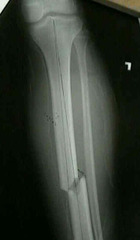

spiral bone

Front

line spirals around shaft of bone (caused by twisting)

oblique fracture

fracture at an angle to the bone

transverse fracture

complete fracture that is straight across the bone at right angles to the long axis of the bone

comminuted fracture

fracture in which bone is shattered, splintered or crushed into many small pieces or fragments